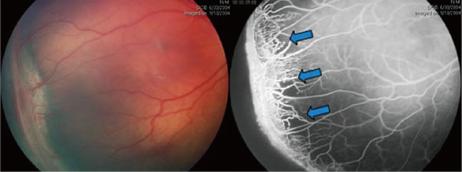

视网膜成像技术是一个将 3D 视网膜结构转变为 2D 平面图像的过程,常用于眼科疾病的检测中。

眼底成像